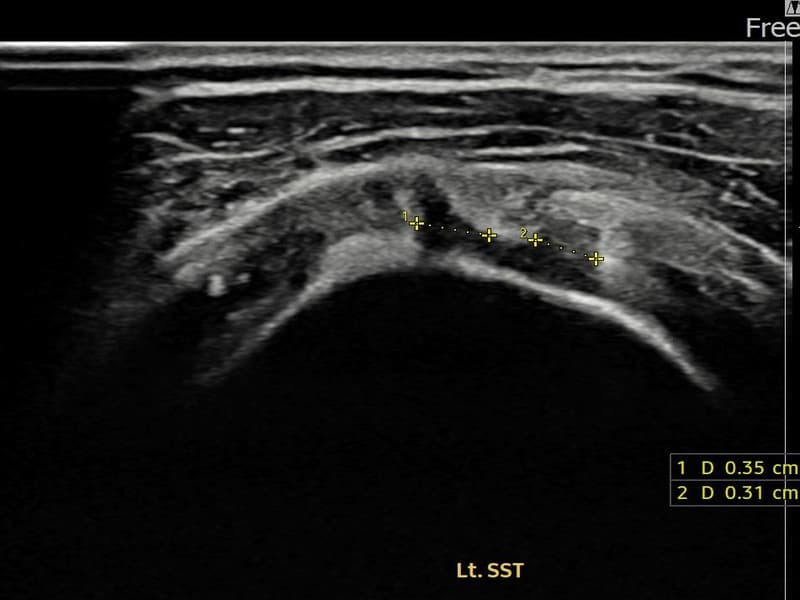

超声确认左侧 冈上肌腱 关节面侧部分撕裂(3.5mm × 3.1mm (부분파열))。缩小缝合术后肌腱连续性恢复,患者回归正常生活。

术前

术前超声确认左侧 冈上肌腱 关节面侧部分撕裂,左侧冈上肌腱回声不连续伴肌腱缺损(3.5mm × 3.1mm (부분파열))。术后超声显示撕裂部位充满再生组织,肌腱连续性恢复,回声模式正常化。

该患者持续肩痛。详细超声检查确认左侧 冈上肌腱 关节面侧部分撕裂(缺损:3.5mm × 3.1mm (부분파열))。在超声引导下实施非手术缩小缝合术。术后佩戴支具约4-6周,随后进行分阶段康复锻炼。随访超声确认肌腱连续性恢复、结构稳定,患者顺利回归日常生活。